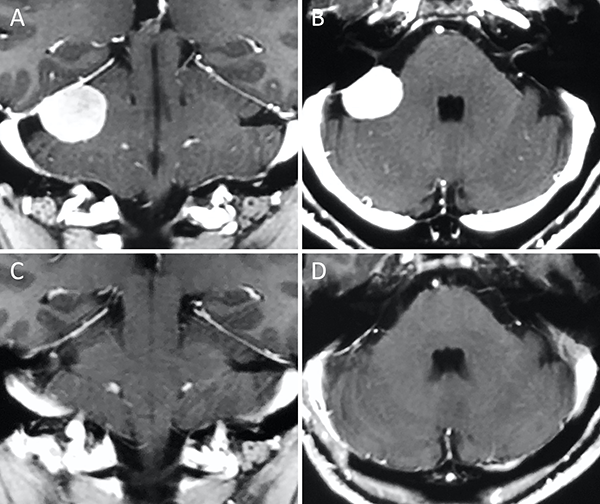

Figura 10. Meningioma del foramen magno lateral. A-B: RM preoperatoria; C-D: RM postoperatoria.